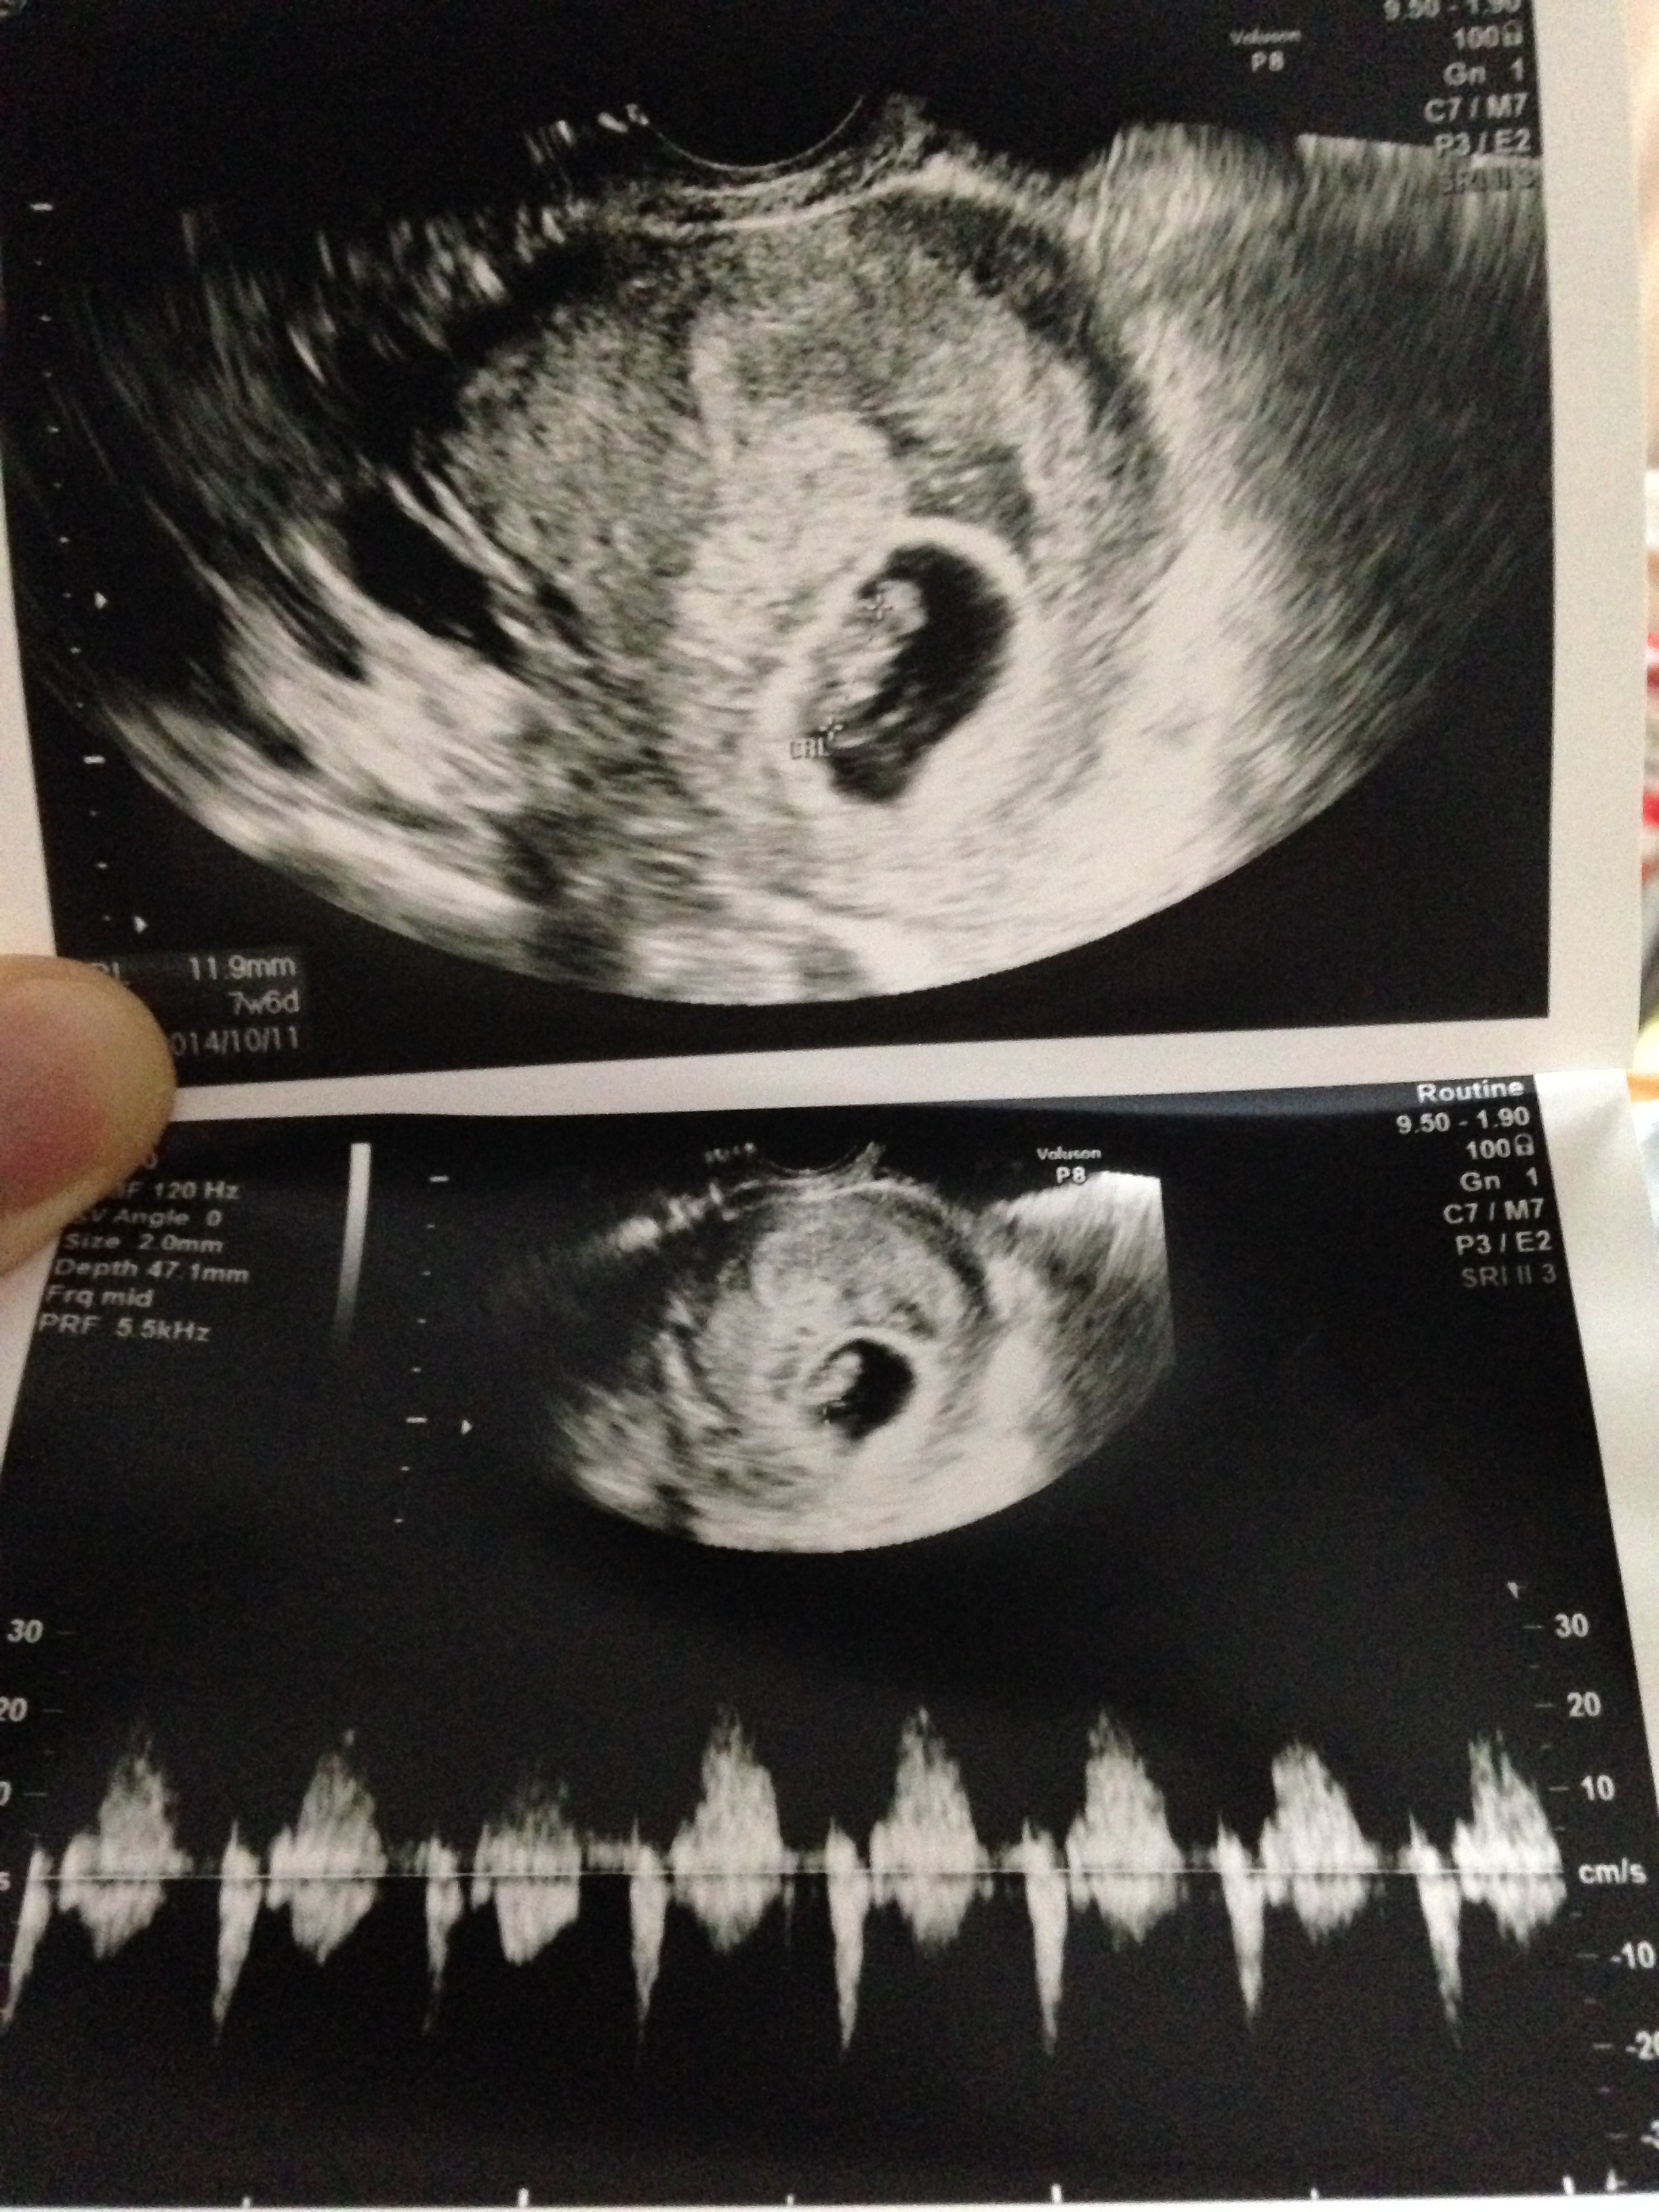

検診行ってきました。

今回も無事に成長してくれていて、良かったです。

出血はかなり終わってきてますが、そうかと思うとまた出てきたりしてました。でもそれももう大丈夫そうだねとの診断で、今回も薬は処方されずに済みました。

この土曜日から8週の計算。

胎芽の大きさからも、やはり出産予定日は10月11日だそうです。